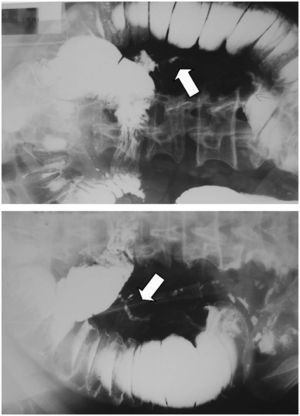

En una tomografía computarizada urgente se confirmó la dilatación de asas del yeyuno con engrosamiento de la pared intestinal y efecto de masa intraluminal (fig. 3). Al ser valorados por cirugía, se practicó laparotomía y se comprueba la existencia de un tumor en el segmento medio del yeyuno de unos 7cm, sin adenopatías ni lesiones tumorales hepáticas, y se practica una resección con anastomosis término-terminal.